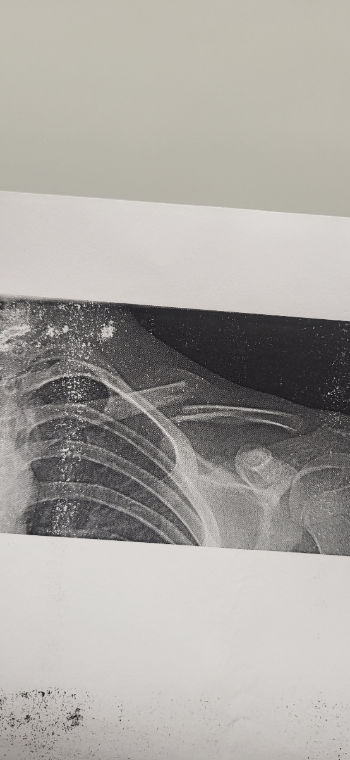

That's the broken clavicle

Reply OwO COD irl, tried diving into a tactical roll and snapped my clavicle on my gun